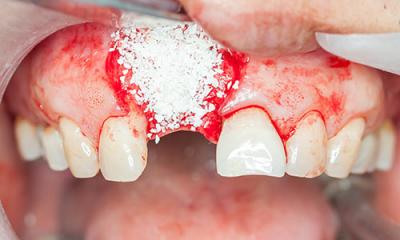

Отсутствие одного или нескольких зубов в ряду приводит к изменениям костной ткани. Если не озаботиться этим вопросом, когда проблема только возникла, впоследствии ситуацию будет сложно решить.

Потребуется наращивание костной ткани. В конечном счёте отсутствие зубов влияет не только на эстетичный вид или артикуляцию, но и на прикус, процессы пищеварения и общее состояние полости рта.